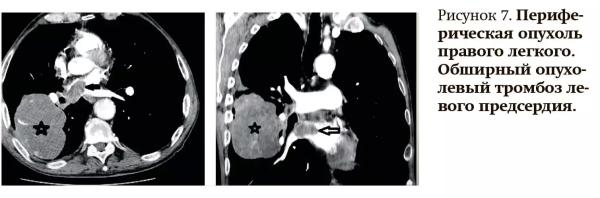

КТ с ангиографией позволяет также выявлять опухолевые тромбозы, при данной патологии это наиболее востребованный метод, поскольку тромбоэмболические осложнения возникают, как правило, уже на поздних стадиях опухолевых процессов, когда выполнить МРТ пациентам становится проблематично из-за их тяжелого общего состояния.

Специалист привел пример диагностического поиска:

— У пациентки с периферической опухолью в правом легком появились жалобы на одышку, отмечались шумы в левом предсердии, изменения на ЭКГ, выполнена Эхо-КГ, свидетельствующая о выраженной сердечной недостаточности. Вследствие этого была предпринята попытка выполнить плановое МРТ-исследование сердца, однако его пришлось прервать, так как пациентка не смогла выполнять команды, исследование оказалось неинформативным. Принято решение о выполнении КТ с ангиографией, на котором четко увидели признаки обширного тромбоза левого предсердия (см. рис. 7).